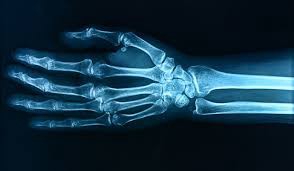

Taking a detailed look at the recent upward trend of FDA approvals for medical devices that use Artificial Intelligence ( ) as well as looking at culture shifts with respect to AI and healthcare in other parts of the world such as the EU, China, UK and Canada AI 2018 was a defining year for medical devices that utilize artificial intelligent algorithms. Even though medical devices have been using ‘software algorithms’ to help assist clinicians, 2018 saw the first FDA approved medical device that uses artificial intelligence and doesn't require a clinician to interpret the input. The last 6 months have seen an increase in FDA approvals and we can expect to see even more approvals. Verbiage used in some of these FDA approvals include ‘ ’, analyzing radio-logical images using machine learning algorithms to detect and diagnose fractures ‘ ’ Using artificial intelligence algorithms, the device is able to determine whether a patient has referable retinopathy IDx-DR and ‘ ’. The verbiage is clearly encouraging as these offer another layer that can help clinicians with decision support. device provides triage or notification that is informed by machine learning, artificial intelligence or other image analysis algorithms tools Equally though there is also the fear that AI will replace e providers, for example Silicon Valley-investor said that machines will substitute 80 percent of doctors in the future in a healthcare scene driven by entrepreneurs, not medical professionals, or when , the godfather of neural networks said that it is ‘ ’. In fact, in May 2017 the Professor of Radiology and Biomedical informatics at Stanford University, mentioned how he received an email from one of his students saying he was thinking about going into radiology but did not know whether it is a viable profession anymore healthcar Vinod Khosla Professor Geoffrey Hinton quite obvious that we should stop training radiologists as image perception algorithms are very soon going to be demonstrably better than humans The U.S. Department of Health and Human Services (HHS), with support from the Robert Wood Johnson Foundation, asked JASON to consider how AI will shape the future of public health, community health, and health care delivery. is an independent group of elite scientists which advises the United States government on matters of science and technology, mostly of a sensitive nature. JASON is a reference to Jason, the mythical Greek hero who was the leader of the Argonauts. JASON Jason of the Argonauts The report states that the design of future health care information systems revolve around questions that need to be answered, one concerned with computer science and the other with fundamental biology. two The computer science question is_, whether an entire medical database can be created and used with the data maintained in a form accessible to human cognition, avoiding the cumbersome and costly translation from analog to digital._ The fundamental biology question is whether the natural coding of information in a human brain is basically analog and not digital. One known fact is a mathematical theorem proved by Marian Pour-El and Ian Richards in 1978. The theorem states that analog computing is in a precise mathematical sense more powerful than digital computing. Pour-El and Richards display a number that is computable with a simple analog device but not computable with any digital device as defined by Alan Turing in his famous paper, “ ’’ in 1937. On Computable Numbers . Their discovery gives us reason to hope that a new generation of computers operating as analog devices may give us databases more user-friendly to us than our present-day digital databases The second fact, supporting the view that the human brain operates as an analog device, is our subjective experience of perception and memory. We experience the visual operation of our brains as a rapid and effortless scanning of pictures moving in space and time. To our subjective view, the brain appears to be primarily a device for the direct comparison of images. We see the images as whole scenes with shape and style, not as collections of pixels. Our perception of continuously moving images does not prove that our brain is an analog device, but it makes this a plausible hypothesis. The question is why now? The truth is there was already a lot of innovative focus on developing AI medical solutions (whether effective or not), but lacked support from effective approval processes. FDA approvals basically mean that you can get paid for services rendered. There has also been a large amount of investment for example Healthcare organizations surveyed by said they planned to invest an average of $32.4 million over the next five years on artificial intelligence. Optum A number of factors are responsible: firstly the was signed into law on December 13, 2016 and was designed to help accelerate medical product development and bring new innovations and advances to patients who need them faster and more efficiently. More specifically the Act specifically exempted certain software products from the definition of ‘medical device’. 21st Century Cures Act (Cures Act) Secondly, Scott Gottlieb became FDA commissioner in May 2017 and under his leadership the FDA has made fighting the crisis of opioid addiction a top priority, advanced initiatives on addressing drug pricing, banned the sale of most flavored e-cigarettes in tens of thousands of convenience stores and gas stations across the country and is expected to propose a ban on menthol in regular cigarettes. He was named “ ” by Time magazine and ranked No 6 by Fortune Magazine's annual survey of the “The World’s 50 Greatest Leaders” in 2018. He also believes that machine learning can help advance healthcare. 50 People Transforming Healthcare in 2018 ‘ ’ Scott Gottlieb, M.D, FDA Commissioner One of the most promising digital health tools is Artificial Intelligence, particularly efforts that use machine learning. There have also been other notable non-AI based advances from the FDA this year such as the approval of 45 novel drugs and biologics which has been the most approved in more than 20 years. Clearly, the FDA is encouraging an environment of innovation. Equally important are the advances in the development of fast hardware Graphics Processor Units (GPUs) allowing for the training of much larger networks, the availability of large labeled datasets both of which have given rise to the ‘data-driven paradigm’ of Deep Learning (DL). Unlike previous eras of excitement over AI, the potential of AI advancement in health may make this era different because of the merging of the following three forces: 1) frustration with the legacy medical system, 2) ubiquity of networked smart devices in our society, 3) acclimation to convenience and at-home services like those provided through Amazon. But…what is Artificial Intelligence? Yes, this may be old news…but how does the US government describe AI? A report by the Executive Office of the President National Science and Technology Council Committee on Technology stated that And will today’s artificial intelligence still be tomorrow’s artificial intelligence? As software becomes increasingly capable, tasks considered as requiring “intelligence” are often removed from the definition, for example, optical character recognition is usually excluded from ‘artificial intelligence’ has become routine technology. This phenomenon is known as the AI effect, which can be described using Tesler’s Theorem “ ” “There is no single definition of AI that is universally accepted by practitioners. Some define AI loosely as a computerized system that exhibits behavior that is commonly thought of as requiring intelligence.” AI is whatever hasn’t been done yet. What does the rest of the world think about health and AI? EU The EU is also introducing new regulations that will apply as of May 26, 2020, s. This means that AI software that currently is excluded from being regulated as software medical devices under the existing regulatory regime, because they do not provide a treatment recommendation, but only a prediction of risk to or predisposition of a disease, may in the future be reclassified as medical devices. regulations that contain additional provisions that specifically address software medical devices. Of particular relevance, software with a medical purpose of “prediction and prognosis” will fall within the scope of the Regulation The European Commission outlines a $24 billion (€20 billion) investment between 2018 and 2020, with the expectation that those funds will come from public and private entities INVESTMENT: China On August 31, 2017, the State Food and Drug Administration (CFDA) released a new version of the “Medical Device Classification Catalog”, which came into effect on August 1, 2018. The original version of the catalog increased from 15 pages to more than 150 pages and the number of name examples increased six-fold to 6609, of which the proportion of medical imaging equipment increased significantly. . The CFDA has also added a specific category corresponding to artificial intelligence-assisted diagnosis, which is embodied in the catalog of analysis and processing of medical images and pathological images China is investing at least $7 billion through 2030, including $2 billion for a research park in Beijing. The Chinese government foresees a $150 billion AI industry at that time. INVESTMENT: UK The UK government announced earlier this year that it plans to invest millions of pounds of government funding to develop AI that is able to diagnose cancer and chronic disease before symptoms have developed, potentially saving 20,000 lives each year. Prime Minister Theresa May challenged health charities, the National Health Service (NHS) and the AI sector to pool data in order to transform the diagnosis of chronic diseases. In response to Theresa May’s challenge Jane Rendall, Managing Director of NHS imaging technology partner Sectra UK & Ireland, said: “ ” The NHS has practically unused archives of millions of diagnostic images that could become one of the most powerful clinical data sets in the world if artificial intelligence is used effectively. Our health service has a wealth of imaging data that it can use to start teaching machines how to recognize parts of the human anatomy, and more importantly, how to recognize abnormalities. The UK government’s ‘ ' published in May 2018 listed the following mission: Use data, Artificial Intelligence and innovation to transform the prevention, early diagnosis and treatment of chronic diseases by 2030. Grand Challenge Policy Paper UK announced a deal between private and public groups that would bring more than $200 million of AI investment into the country INVESTMENT: Canada In 2018 Canada introduced the ‘ ’ initiative, Health Canada established a new division within the Therapeutic Products Directorate’s Medical Devices Bureau to allow for a more targeted pre-market review of digital health technologies, to adapt to rapidly changing technologies in digital health, and to respond to fast innovation cycles. The initiative focuses on a number of key areas including AI. Regulatory Review of Drugs and Devices The Canadian government has committed $125 million to AI research INVESTMENT: List of US healthcare companies that have FDA approved AI medical devices Companies that got FDA approval for AI algorithms in 2018 The Role of the FDA The Food and Drug Administration (FDA) assures that patients and health care providers have timely and continued access to safe, effective, and high-quality medical devices. What is a medical device? A is any apparatus, appliance, software, material, or other article, whether used alone or in combination, including the software intended by its manufacturer to be used specifically for diagnostic and/or therapeutic purposes medical device Medical devices are classified into 3 classes based on the risk, Class I, Class II, or Class III, with Class I being the lowest risk and Class III the highest risk. 3% of devices are are not yet classified by the FDA. % Classification of FDA approved Devices (source: FDA.gov) The FDA regulates over different devices, which are manufactured by more than firms in more than medical device facilities worldwide. 190,000 18,000 21,000 Problems with the current process The FDA’s 510(k) approval process dates from 1976, The 510(k) pathway is the most commonly used premarket review process. In 2017, the FDA cleared 3,173 devices through the pathway, or 82 percent of all devices cleared or approved. Close to 20 percent of current 510(k) approvals are based on predicate devices that are more than 10 years old, a process that could be holding back medical device innovation. Under the 510(k) pathway, device manufacturers use comparative testing against predicate devices — devices already on the market — to show that a new device is as safe and effective as the predicate device. FDA Advances The FDA introduced the De Novo classification for new, novel devices whose type has previously not been classified. It’s for devices that would otherwise be classified into Class III, and provides a means to classify into Class I or II. The De Novo pathway provides a vehicle for establishing new predicates that can reflect modern standards for performance and safety and can serve as the basis for future clearances. As a result, we expect to see more developers take advantage of the De Novo pathway for novel devices. The future of AI in healthcare An Optum survey revealed that 91% of 500 US healthcare leaders said they expect to see a return on investment (ROI) for AI over the next few years. Hospital execs expect to see the ROI in four to five years, while health plans hope to see ROI in three years or less. 36% of respondents said they expect AI to improve patient experience, 33% think AI will decrease per-capita cost of care, and 31% believe AI will improve health outcomes. “Analytics isn’t the end, it’s the beginning — it’s what you do with the insights to drive care improvement and reduce administrative waste,” said Optum Enterprise Analytics SVP and COO Steve Griffiths. “For AI to successfully solve healthcare’s biggest challenges, organizations need to employ a unique combination of curated data, analytics and healthcare expertise.” Artificial intelligence in healthcare does present a whole new set of challenges around data privacy, security and ethics — challenges that are compounded by the fact that most algorithms need access to massive data sets for training and validation. These algorithms in some cases also ‘predict’ outcomes without the full knowledge of how the prediction was made. They are subject to bias and not fully transparent. This is leading to an emerging field of aims to create new AI methods that are accountable to human reasoning. explainable AI Balancing the risks and rewards of AI in healthcare will require collaborative effort from technology developers, regulators, end-users and consumers. Amrit Virdee Machine Learning Engineer | Health Informatics | Pharmacist | Mapping Medication. Some of my other posts: _Before any predictive ML models can be applied to a data set it is important to thoroughly understand the data. Using…_hackernoon.com Visualizing State Drug Utilization Data Sets _Experimenting with simple data augmentation parameters to get the best results_towardsdatascience.com Data Augmentation Experimentation References: _Source: Thinkstock - Healthcare organizations surveyed by Optum said they planned to invest an average of $32.4 million…_hitinfrastructure.com Healthcare Firms to Spend Average of $32M on Artificial Intelligence _In July, the Food and Drug Administration issued guidance on three topics important to the future of medical…_www.forbes.com Artificial Intelligence, Machine Learning, And The FDA _For the first time, the Food and Drug Administration has approved marketing a medical device that uses artificial…_www.modernhealthcare.com FDA grants first approval to autonomous AI-powered medical device _Remarks by Scott Gottlieb, M.D.Commissioner of Food and DrugsAcademy Health's 2018 Health DatapaloozaWashington…_www.fda.gov Transforming FDA's Approach to Digital Health _Eighty years ago today, President Roosevelt signed the Federal Food, Drug, and Cosmetic Act ("FD&C Act"). In…_www.healthlawadvisor.com 21st Century Cures Act | Health Law Advisor _Machines will replace 80 percent of doctors in a healthcare future that will be driven by entrepreneurs, not medical…_www.wired.co.uk Vinod Khosla: Machines will replace 80 percent of doctors _Hype and fears surround artificial intelligence taking jobs in healthcare. Will it render physicians obsolete? Will it…_medicalfuturist.com 5 Reasons Why Artificial Intelligence Won't Replace Physicians - The Medical Futurist _The UK government has announced plans to invest millions of pounds of government funding to develop AI that is able to…_thejournalofmhealth-com.cdn.ampproject.org UK to Invest Millions in Healthcare AI _The Industrial Strategy sets out Grand Challenges to put the UK at the forefront of the industries of the future. As…_www.gov.uk The Grand Challenge missions _The United States and China currently dominate the world of artificial intelligence, but used very different approaches…_qz.com AI is the new space race. Here's what the biggest countries are doing